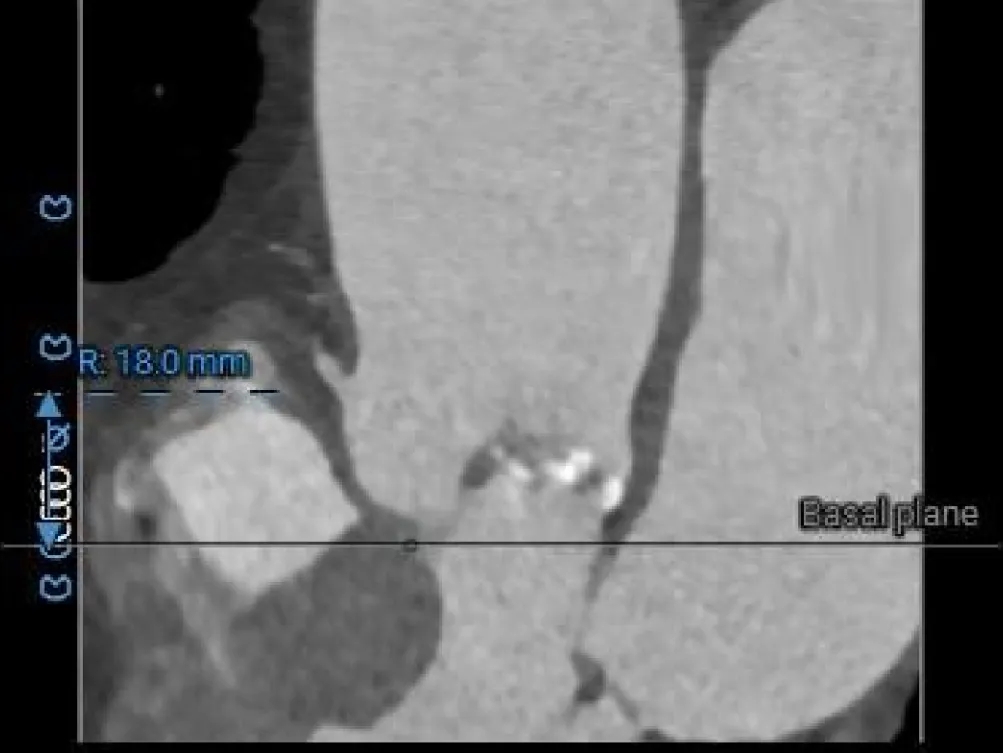

冠脉风险评估

LCA Height

RCA Height

LCA & Leaflet

RCA & Leaflet